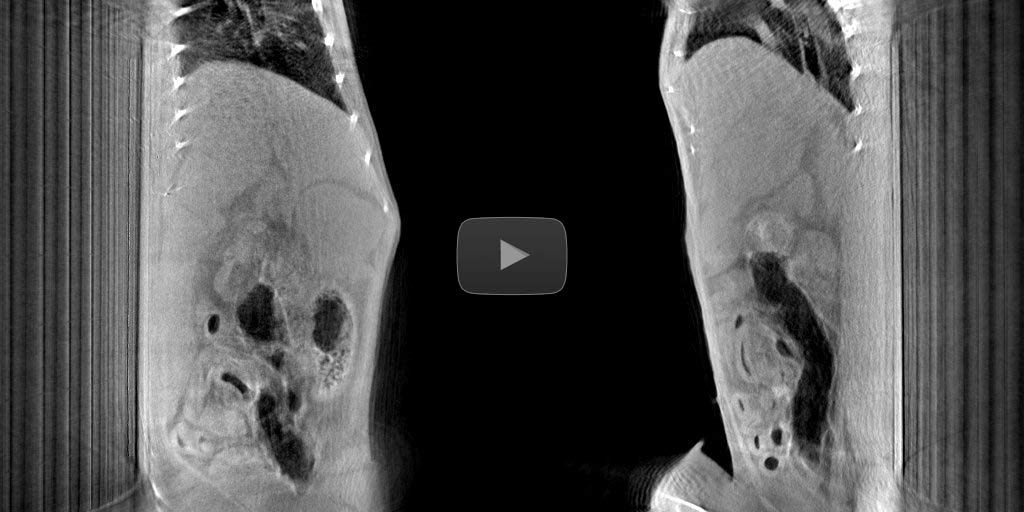

Breathing motion management without use of external breath registration devices.

Converting input views into 4D domain.

Breath cycle detection directly on input views